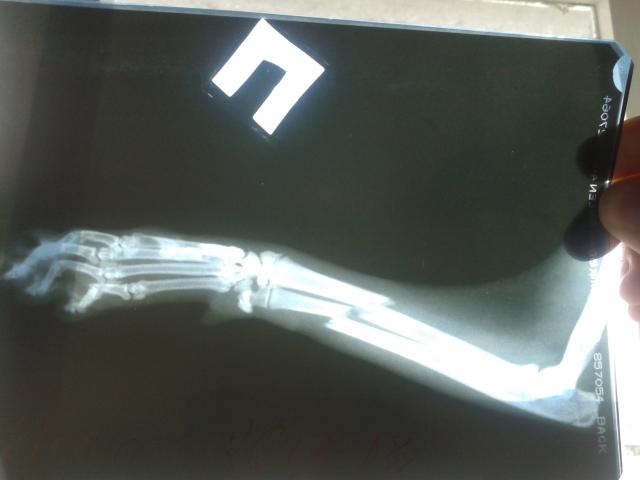

Перелом лапы со смещением

Здравствуйте! Помогите, пожалуйста, разобраться. 26 июня моя кошечка выпала из окна 8 этажа на бетонную крышу подъезда. Сделали узи ОБП и рентген передней правой лапки. На узи все в порядке, а вот с лапой проблема. Оказалось что у нее перелом со смещением. 28 июня сделали операцию, поставили спицы. 4 июля я сделала контрольный снимок и не поняла… Это так и должны быть кости или нам плохо сделали операцию? Добавляю снимки рентгена и лапы кошки после операции.

Можно было бы и лучше сделать, но уж как получилось. Погрешности не критичны, кости срастутся, двигательные функции полностью восстановятся.